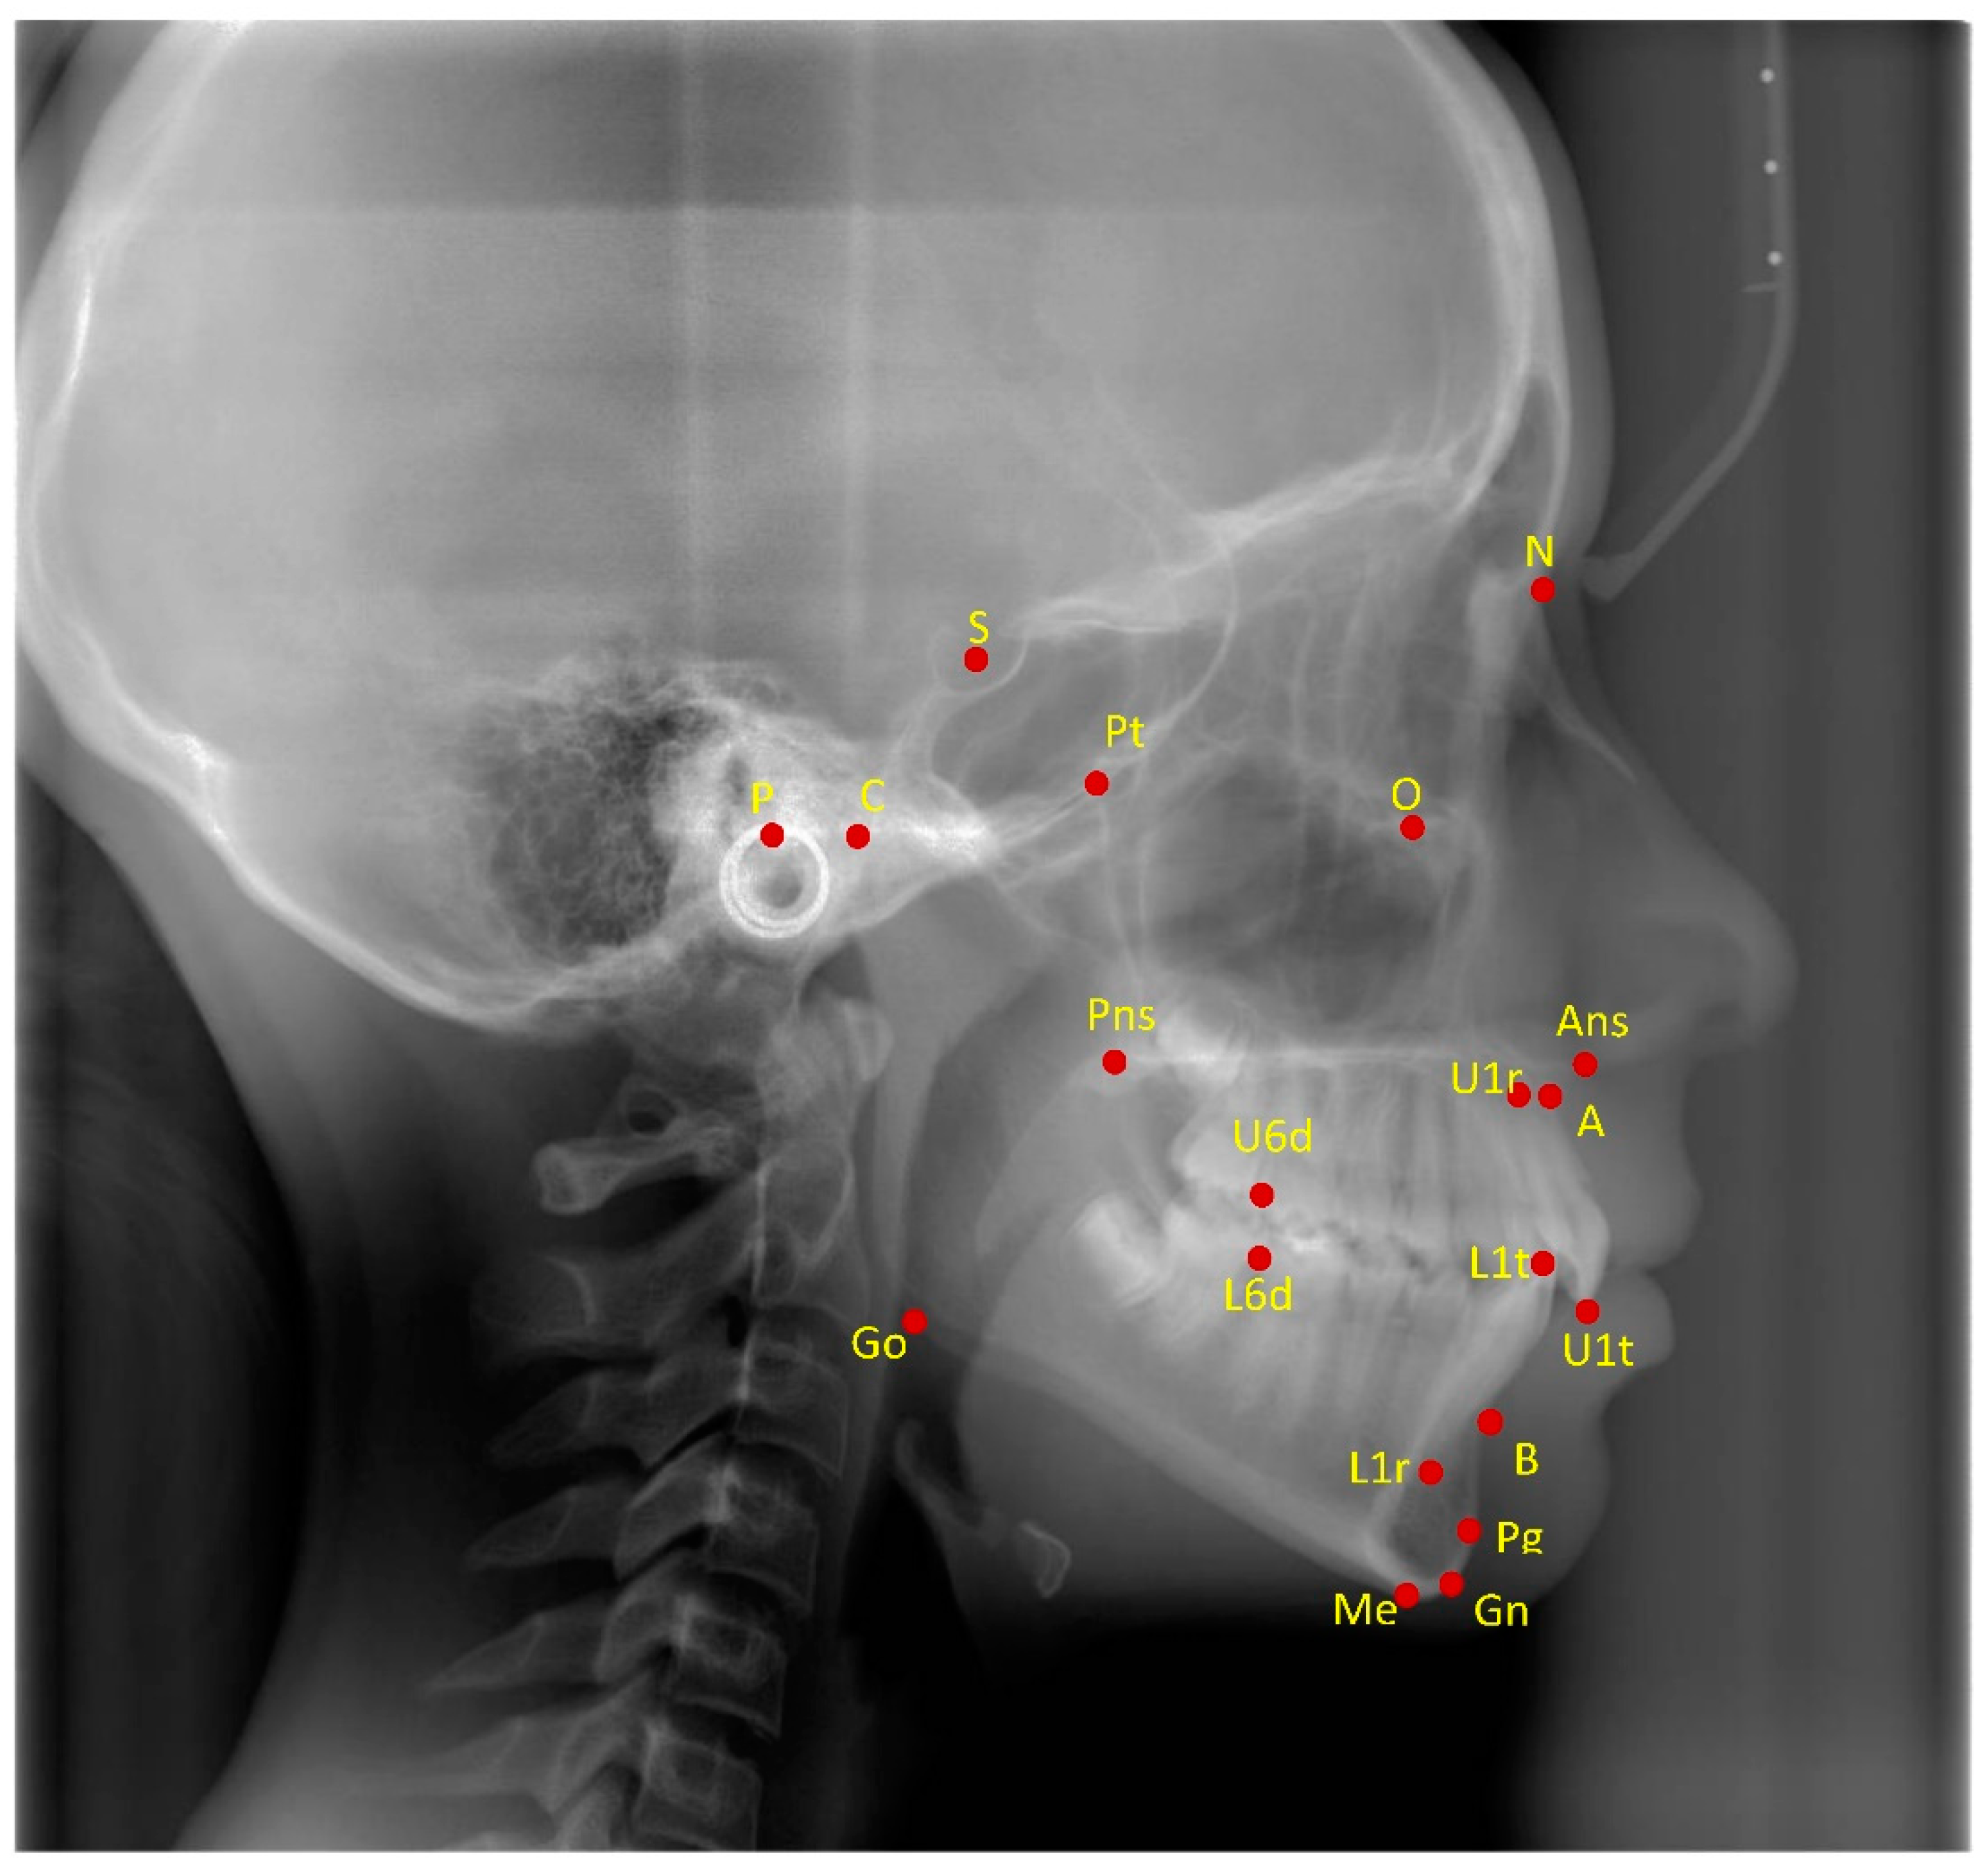

| Sagittal Skeletal | Interdental |

|---|---|

| SNA (°) | Overjet (mm) |

| SNPg (°) | Overbite (mm) |

| ANPg (°) | Molar relation (mm) |

| WITS (mm) | Maxillary dentoalveolar |

| Co-Gn (mm) | U1 to palatal plane (°) |

| Vertical skeletal | U1-NPo (mm) |

| SN to palatal plane (°) | U6-PT Vertical (mm) |

| SN to mandibular plane (°) | Mandibular dentoalveolar |

| Palatal plane to mandibular plane (°) | L1 to mandibular plane (°) |

| CoGoMe (°) | |

| Co-Go (mm) |